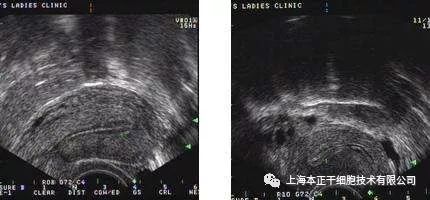

图3:排卵前摘除宫内节育器后子宫内膜变薄

图4:子宫内膜发育良好,低阻力血管达4区。

2014年,印度新德里全印度医学院妇产科和干细胞研究所的Singh博士对一位重度IUA病人进行了自体骨髓间充质干细胞治疗,病人治疗前均有继发性闭经或不孕病史,且行传统宫腔粘连分解术及雌激素治疗失败,间充质干细胞治疗后 3、6、9个月,所有病人内膜厚度较治疗前均有明显增加,其中5例病人恢复了闭经。

图1:患者移植前子宫内膜厚度

图2:同一患者移植后子宫内膜厚度